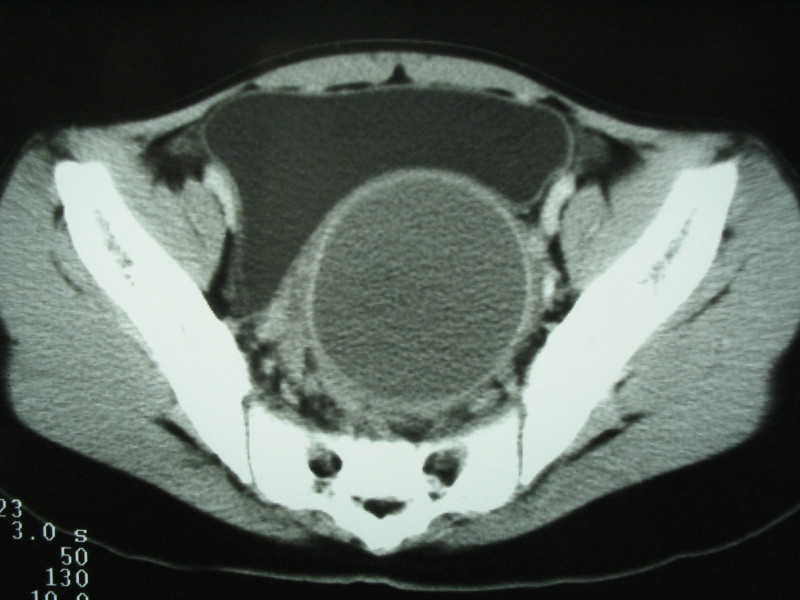

以下是引用xiaoniu在2009-2-13 18:04:00的发言:[br]病变表现在阴道及子宫的位置区,成圆形低密度区,外形光整,建议询问病史来过月经吗,疼痛有规律吗 等,考虑阴道子宫积液或积血,原因应为女性生殖器官发育异常:正常管道形成受阻所致的异常处女膜闭锁

以下是引用随光逐影在2009-2-13 18:13:00的发言:[br]考虑宫腔积液或积血(可能为先天性处女膜闭锁所致,请结合临床检查)。